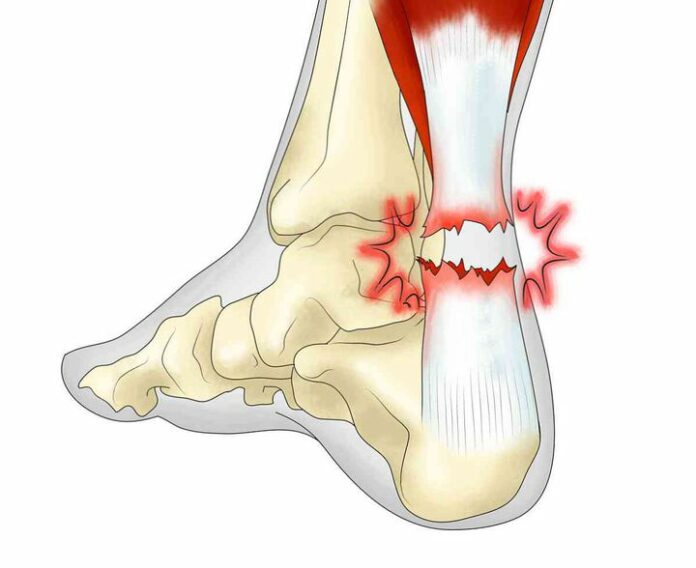

В последствие операцията се извършва от съвсем други лица . Въпросната операция се оказва неуспешна . Самата операция на ахилеса е извършена БЕЗ ЯМР и е изпуснат да се зашие главен сегмент от ахилеса . В следствие от неуспешната операция се получава огромен хематом и Даниел отива в София на второ и трето мнение . ( от клуба и докторите от Варна категорично отказват да се прави ЯМР и се твърди , че операцията е извършена успешно )

Това е крайният резултат от първата операция ,след ЯМР в София. След второ и трето мнение от лекари , се налага Даниел да влезне по спешност за втора операция . Това са хората , към които трябва да бъдат отправени благодарностите и аз , брат ми и семейството ни изказваме благодарностите си към тях. Ръководството обеща лично на майка ми цялата сума от операцията + цялата рехабилитация на брат ми да бъде покрита. Всичко до сега след първата псевдо-операция се поема от нашето семейство . Днес и официално получихме отказ от застрахователите за покриване на медицинските разноски на футболиста . Пиша ви, за да сте запознати с цялата ситуация , Дани е по-добре , възстановява се , благодари ви за подкрепата и се надява в най-скоро време да се видите отново . А ние , като негово семейство ще потърсим отговорност на лицата замесени в тази ситуация , защото в крайна сметка здравето е най-важното.